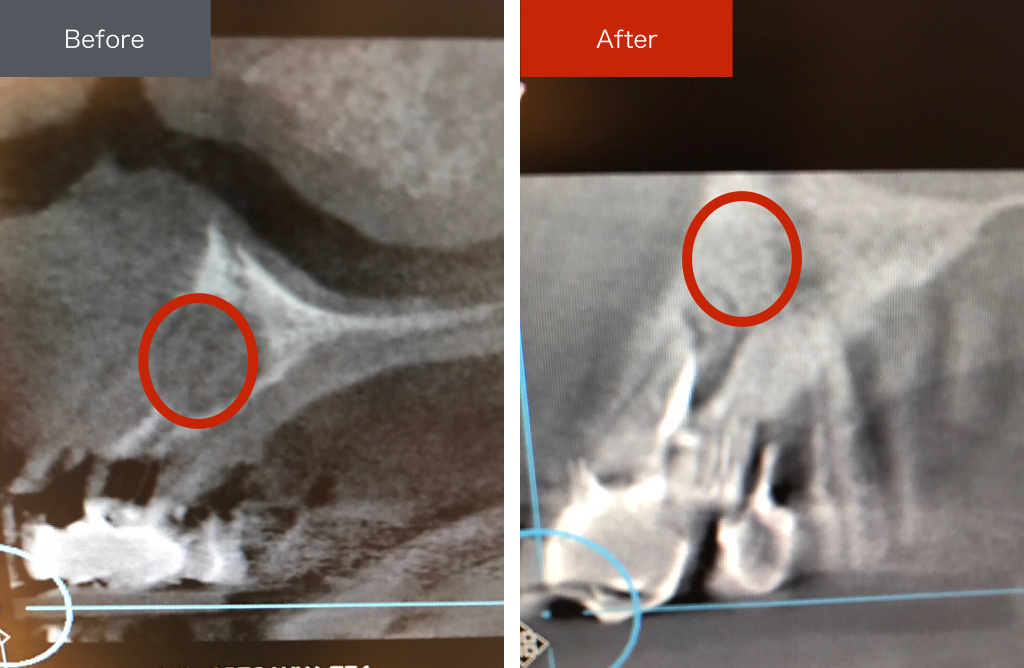

前医でインプラントの埋入角度が悪く、インプラント周囲炎になってしまった患者様の症例です。

インプラントが虫歯になることはありませんが、インプラント周囲炎というインプラントの歯周病にはなります。

インプラント周囲炎の主な原因は汚れ(菌)と力です。このように斜めに埋入されているインプラントは、真っ直ぐ埋入されているものに比べて汚れも溜まりやすく、噛む力も斜めにかかってしまうため、インプラント周囲炎になるリスクが大幅に高くなります。

この患者様は内側の骨が大幅に溶けてしまっていたので、前のインプラントを撤去して、骨を再生させると同時にインプラントを正しい位置と角度で埋入し直しました。溶けてしまっていた骨が治っていることもレントゲンでご確認いただけるかと思います。

インプラントは「どこの位置にどのような角度で入れるか」によって、一生使い続けられるかどうかの期待値が大きく異なります。値段だけを基準にクリニックを決めるのではなく、信用できる歯医医師と治療を進めることをお勧めします。